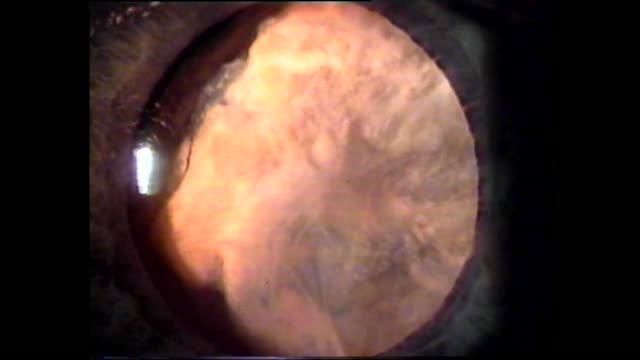

Leukocoria: Novel Solution

Robert Osher, MD